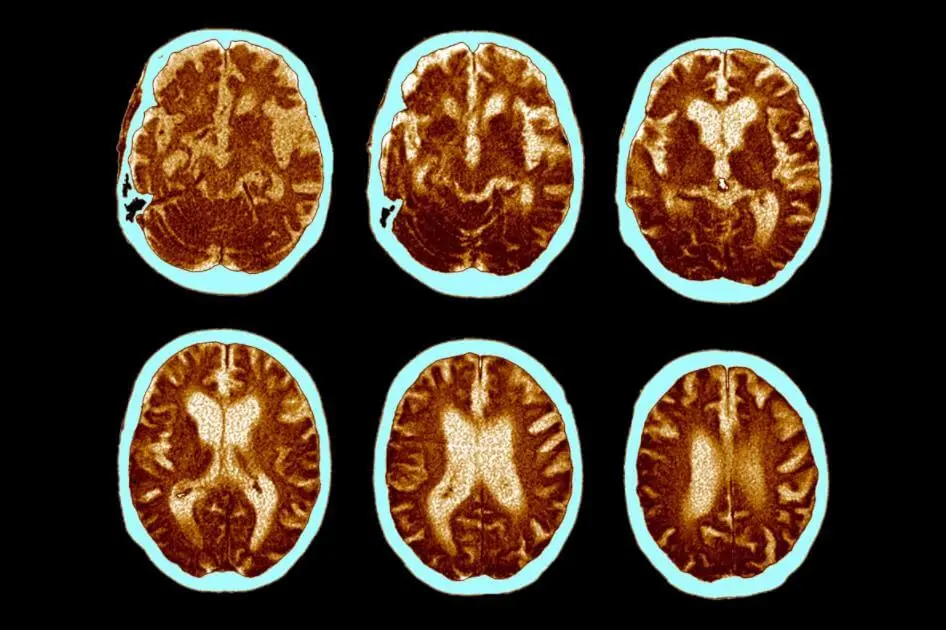

Above:A 68-year-old woman with a 10-year history of cognitive impairment showed marked hypometabolism with a pattern suggestive of Alzheimer's disease prior to PET scan, PET scan after treatment with inhibitor (RI). Gradually approaching the normal brain, the patient's cognitive ability improved significantly.